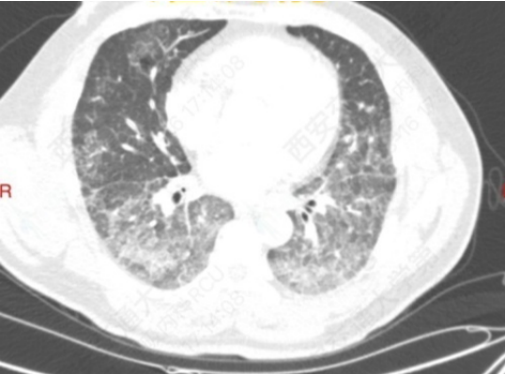

病例3:危重的肺泡蛋白沉积症

患者,男性,39岁,双肺弥漫性间质性炎(图14)PaO53 mmHg、Ⅰ型呼吸衰竭,高流量吸氧及无创呼吸机辅助通气无明显改善,收住RICU,行冷冻肺活检提示:肺泡蛋白沉积症(图15)

图片

图14  患者胸部CT

图15  肺活检病理结果

MDT意见:难以纠正的呼吸衰竭;肺功能差;灌洗过程中可能出现急性肺水肿;难以耐受长时间全身麻醉。予清醒VV-ECMO+大容量肺泡灌洗。患者氧合得以纠正,病情好转(图16)

图16  患者肺泡灌洗前后比较

思考:①对于双肺弥漫性间质性病变患者,明确诊断非常关键。受目前医疗技术的限制,冷冻肺活检是各指南共识均推荐的重要方法,在危重症患者的救治过程中,不要因为此项技术有较大的出血风险就放弃,而需要依据操作流程,细心、大胆,尽可能为患者明确诊断,争取治疗时机。②此例是在ECMO支持下为患者争取了救治机会,经第一次双肺大容量灌洗后,氧合明显改善,后续治疗不再依赖ECMO进行。